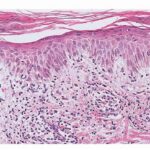

Histopathology. The small-plaque parapsoriasis shows focal epidermal involvement consisting of slight spongiosis, exocytosis of lymphocytes, mild acanthosis, and parakeratosis . Elongated mounds of parakeratosis with collections of plasma above a basket-weave cornified layer is a characteristic finding . In the papillary dermis, there is a mild superficial perivascular lymphocytic infiltrate that in some instances is more pronounced and resembles that seen in the large plaque type; such cases require inclusion in the largeplaque category . It must be conceded that, in some instances, a clinical or histologic distinction of small-plaque parapsoriasis from large-plaque parapsoriasis is difficult, so that only the subsequent course decides the issue . |